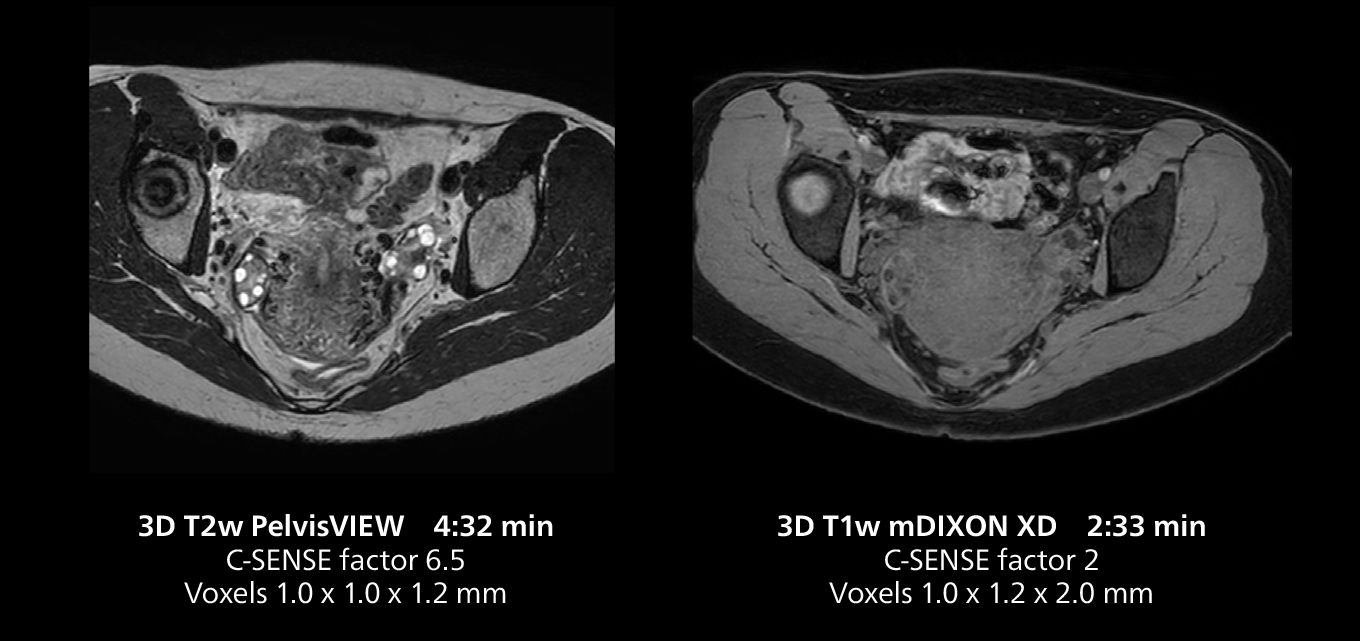

Female pelvis imaging

This MRI case illustrates good resolution and imaging quality obtained within reasonable scan times using the MR 5300 1.5T system with the anterior torso cardiac coil that allows use of a large field of view (FOV).

Dr. Gellée highlights the robust free-breathing scans as “the feature that makes the biggest difference in my daily work. The 3D free breathing sequences are very reproducible, and the axial acquisition is very good. For example, in endometriosis, which is one of my focus areas, it provides high contrast and good resolution so that I can see small details. We also use free breathing for liver and pancreas imaging. In multi-phase liver studies, 4D Free Breathing delivers 3-second temporal resolution, making a dynamic scan with more than one arterial phase possible.”

Dr. Gellée also appreciates the large FOV imaging that the system makes possible. “I can image the intestines in a single acquisition by using a large field of view, which is enabled by combining coils to get more coverage. The images are of good quality and look very crisp.”